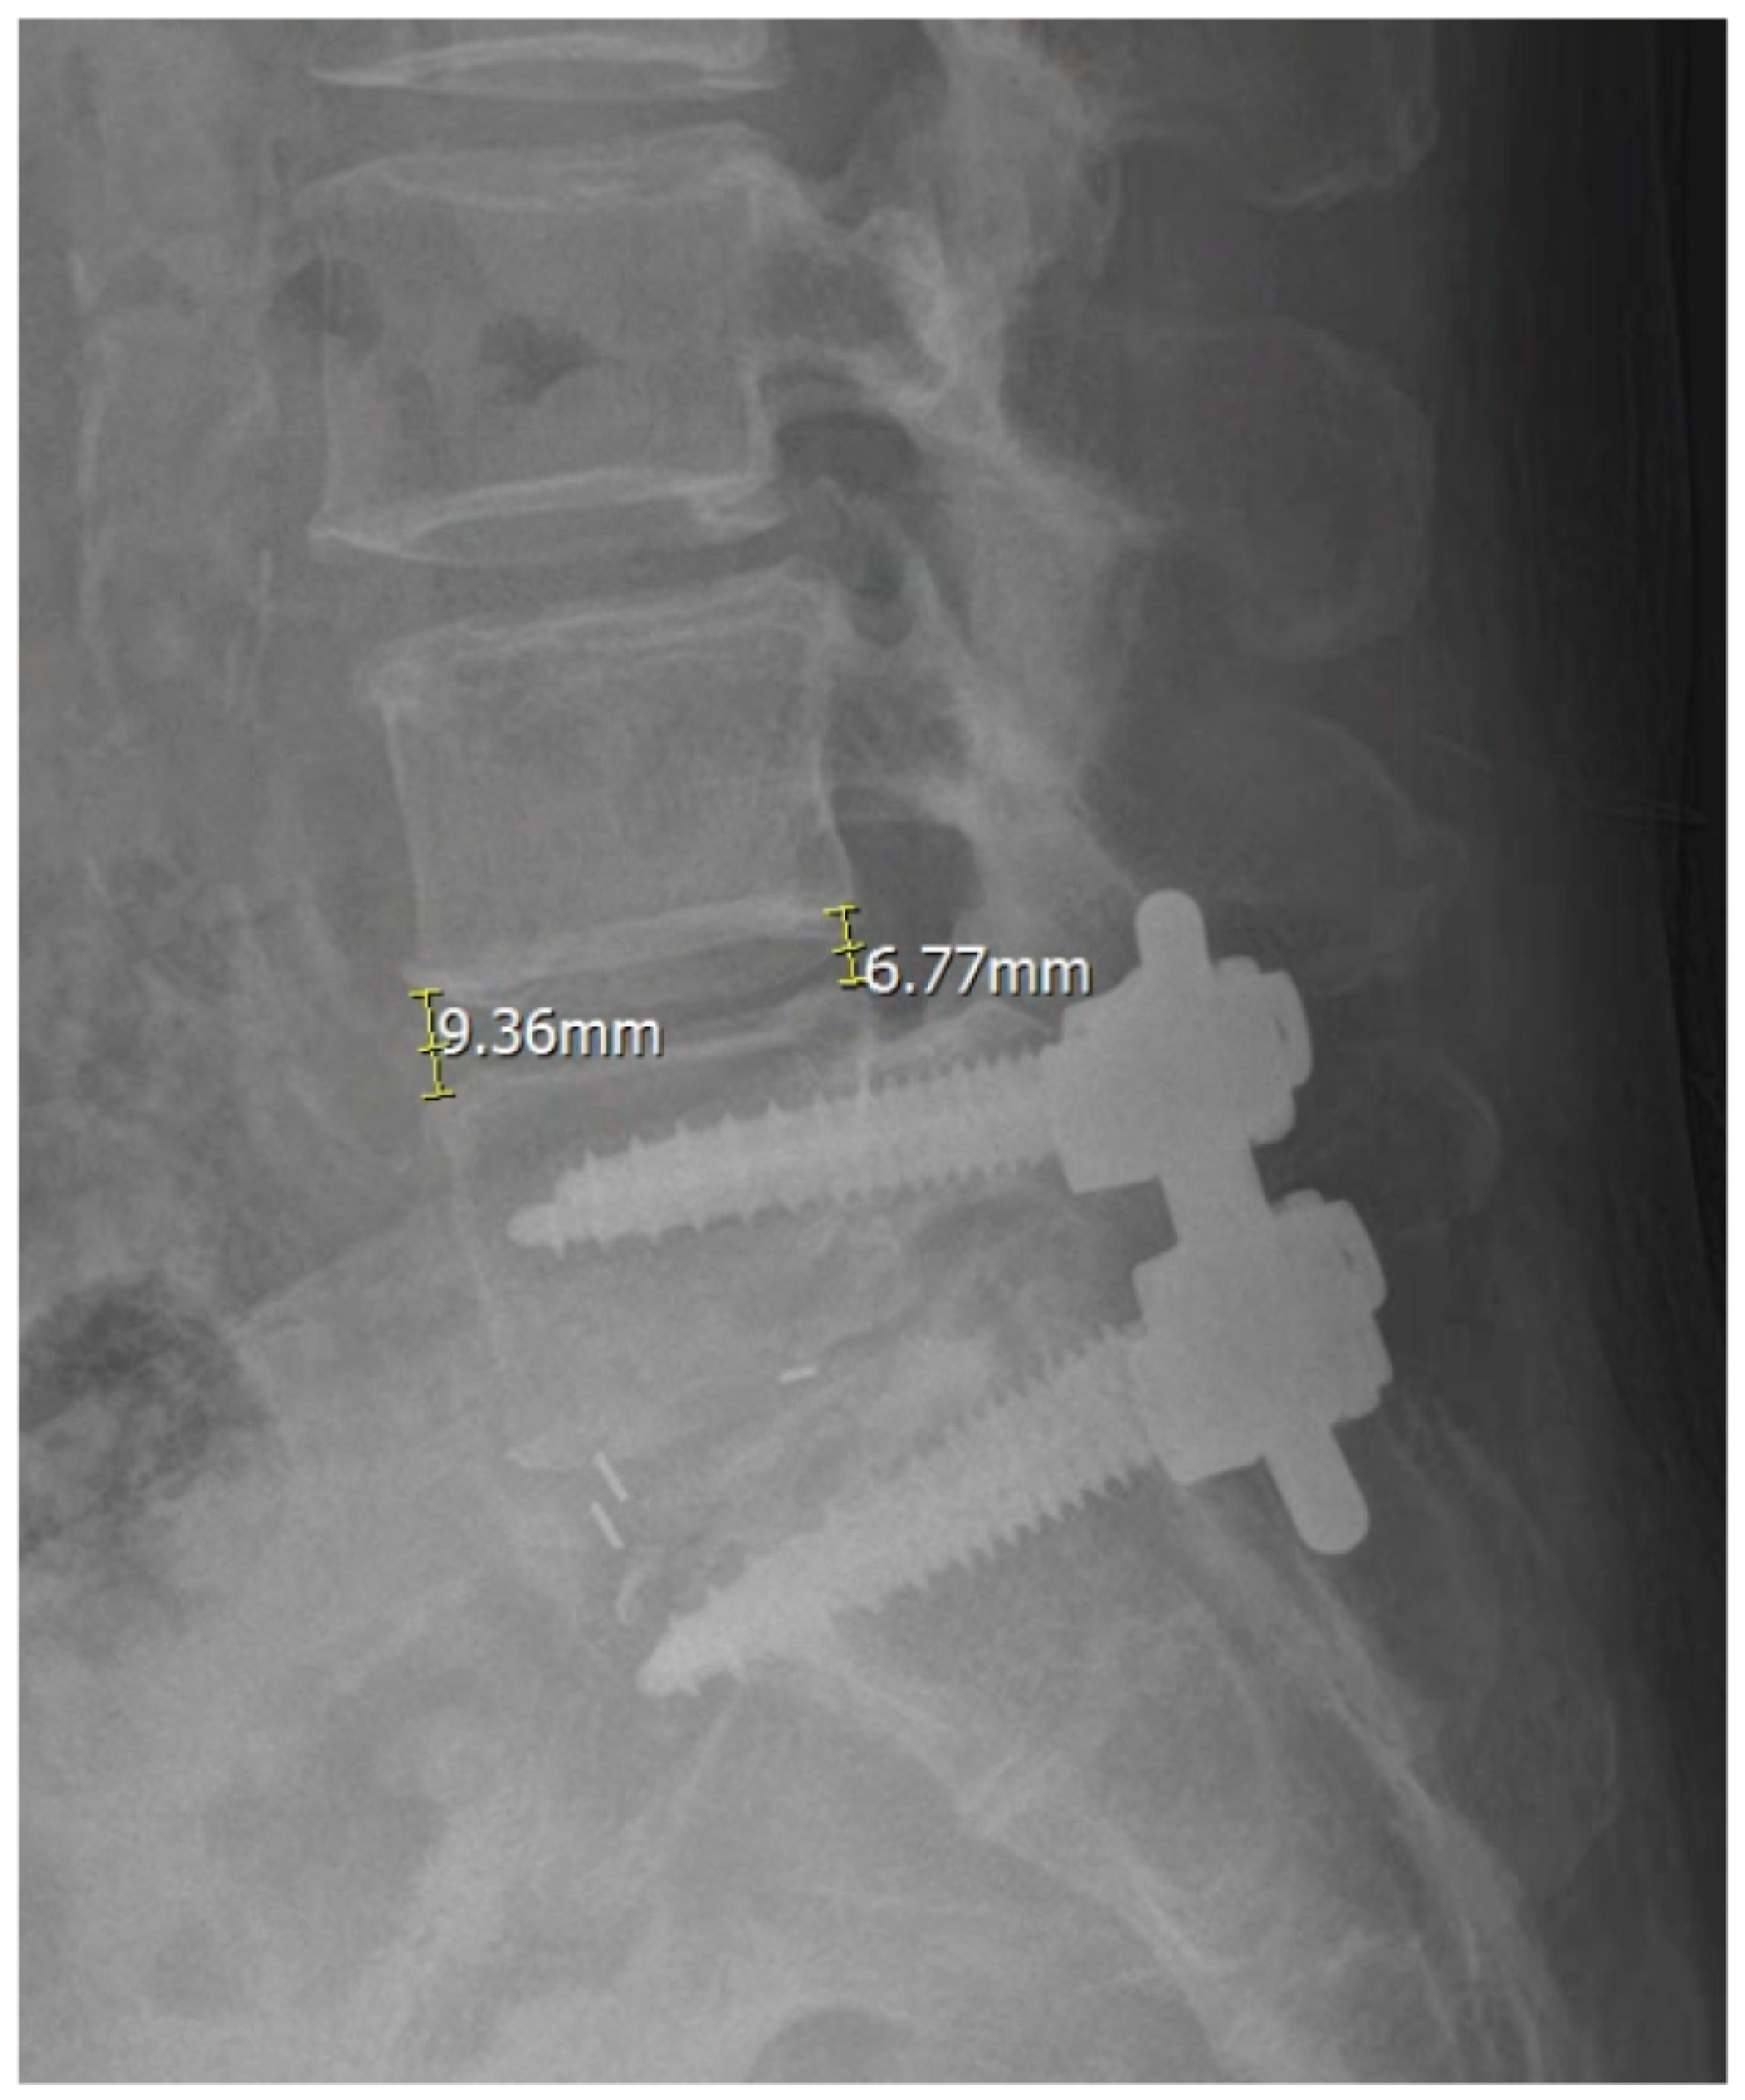

3.5. Illustrative Case